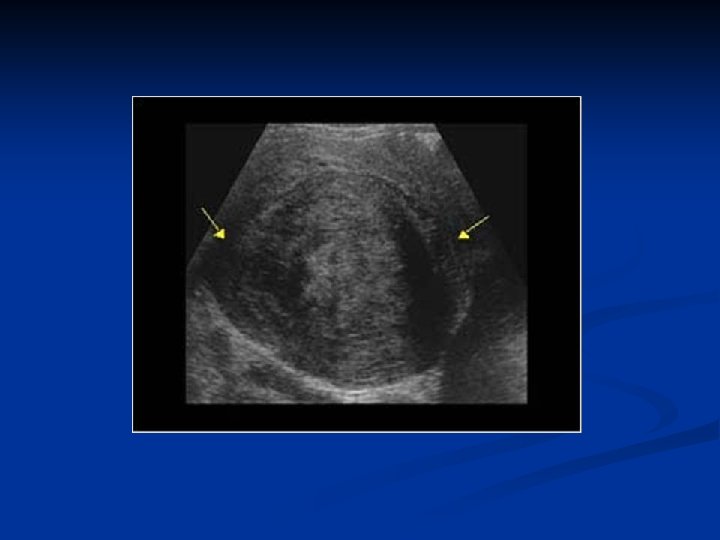

Ovarian Neoplasms-Germ Cell Tumors n Mature Teratomas n Solid n n mature teratomas Usu unilat rare n Mature n n cystic teratomas (dermoid cysts) %95 of all germ cell tumors and %20 of all ovarian tumors Derived from any of the 3 germ cell layers, well differentiated Usually asymptomatic Mostly seen in 20 -40 years of age

Ovarian Neoplasms-Germ Cell Tumors n n n %10 -15 bilateral Rarely bigger than 15 cm Usually unilocular Filled with yellowish coloured fluid with hair, tooth and bones in it There is an irregular solid nodule (Rokitansky nodule) on the inner side of the cyst which consists bones, cartilages and/or fat Complications n n Tortion ( the most)- usually in children and women Rupture ( very rare) Infection Malign transformation ( %1 -2) ( mostly squam. cell carsinoma)

Ovarian Neoplasms-Germ Cell Tumors n n n Diagnosis: TV-USG, MRI Therapy: ovarian cystectomi + examination of the contralateral ovary Immature Teratomas n n n Most common malign germ cell tumors Different from mature cystic teratomas can be seen at all ages, but usu. at reproduc. ages esp first three decades Usu grows quickly outside the capsule and causes adhesions to nearby structures and peritonel cavity implants Usu unilat, AFP may rise 9 -28 cm